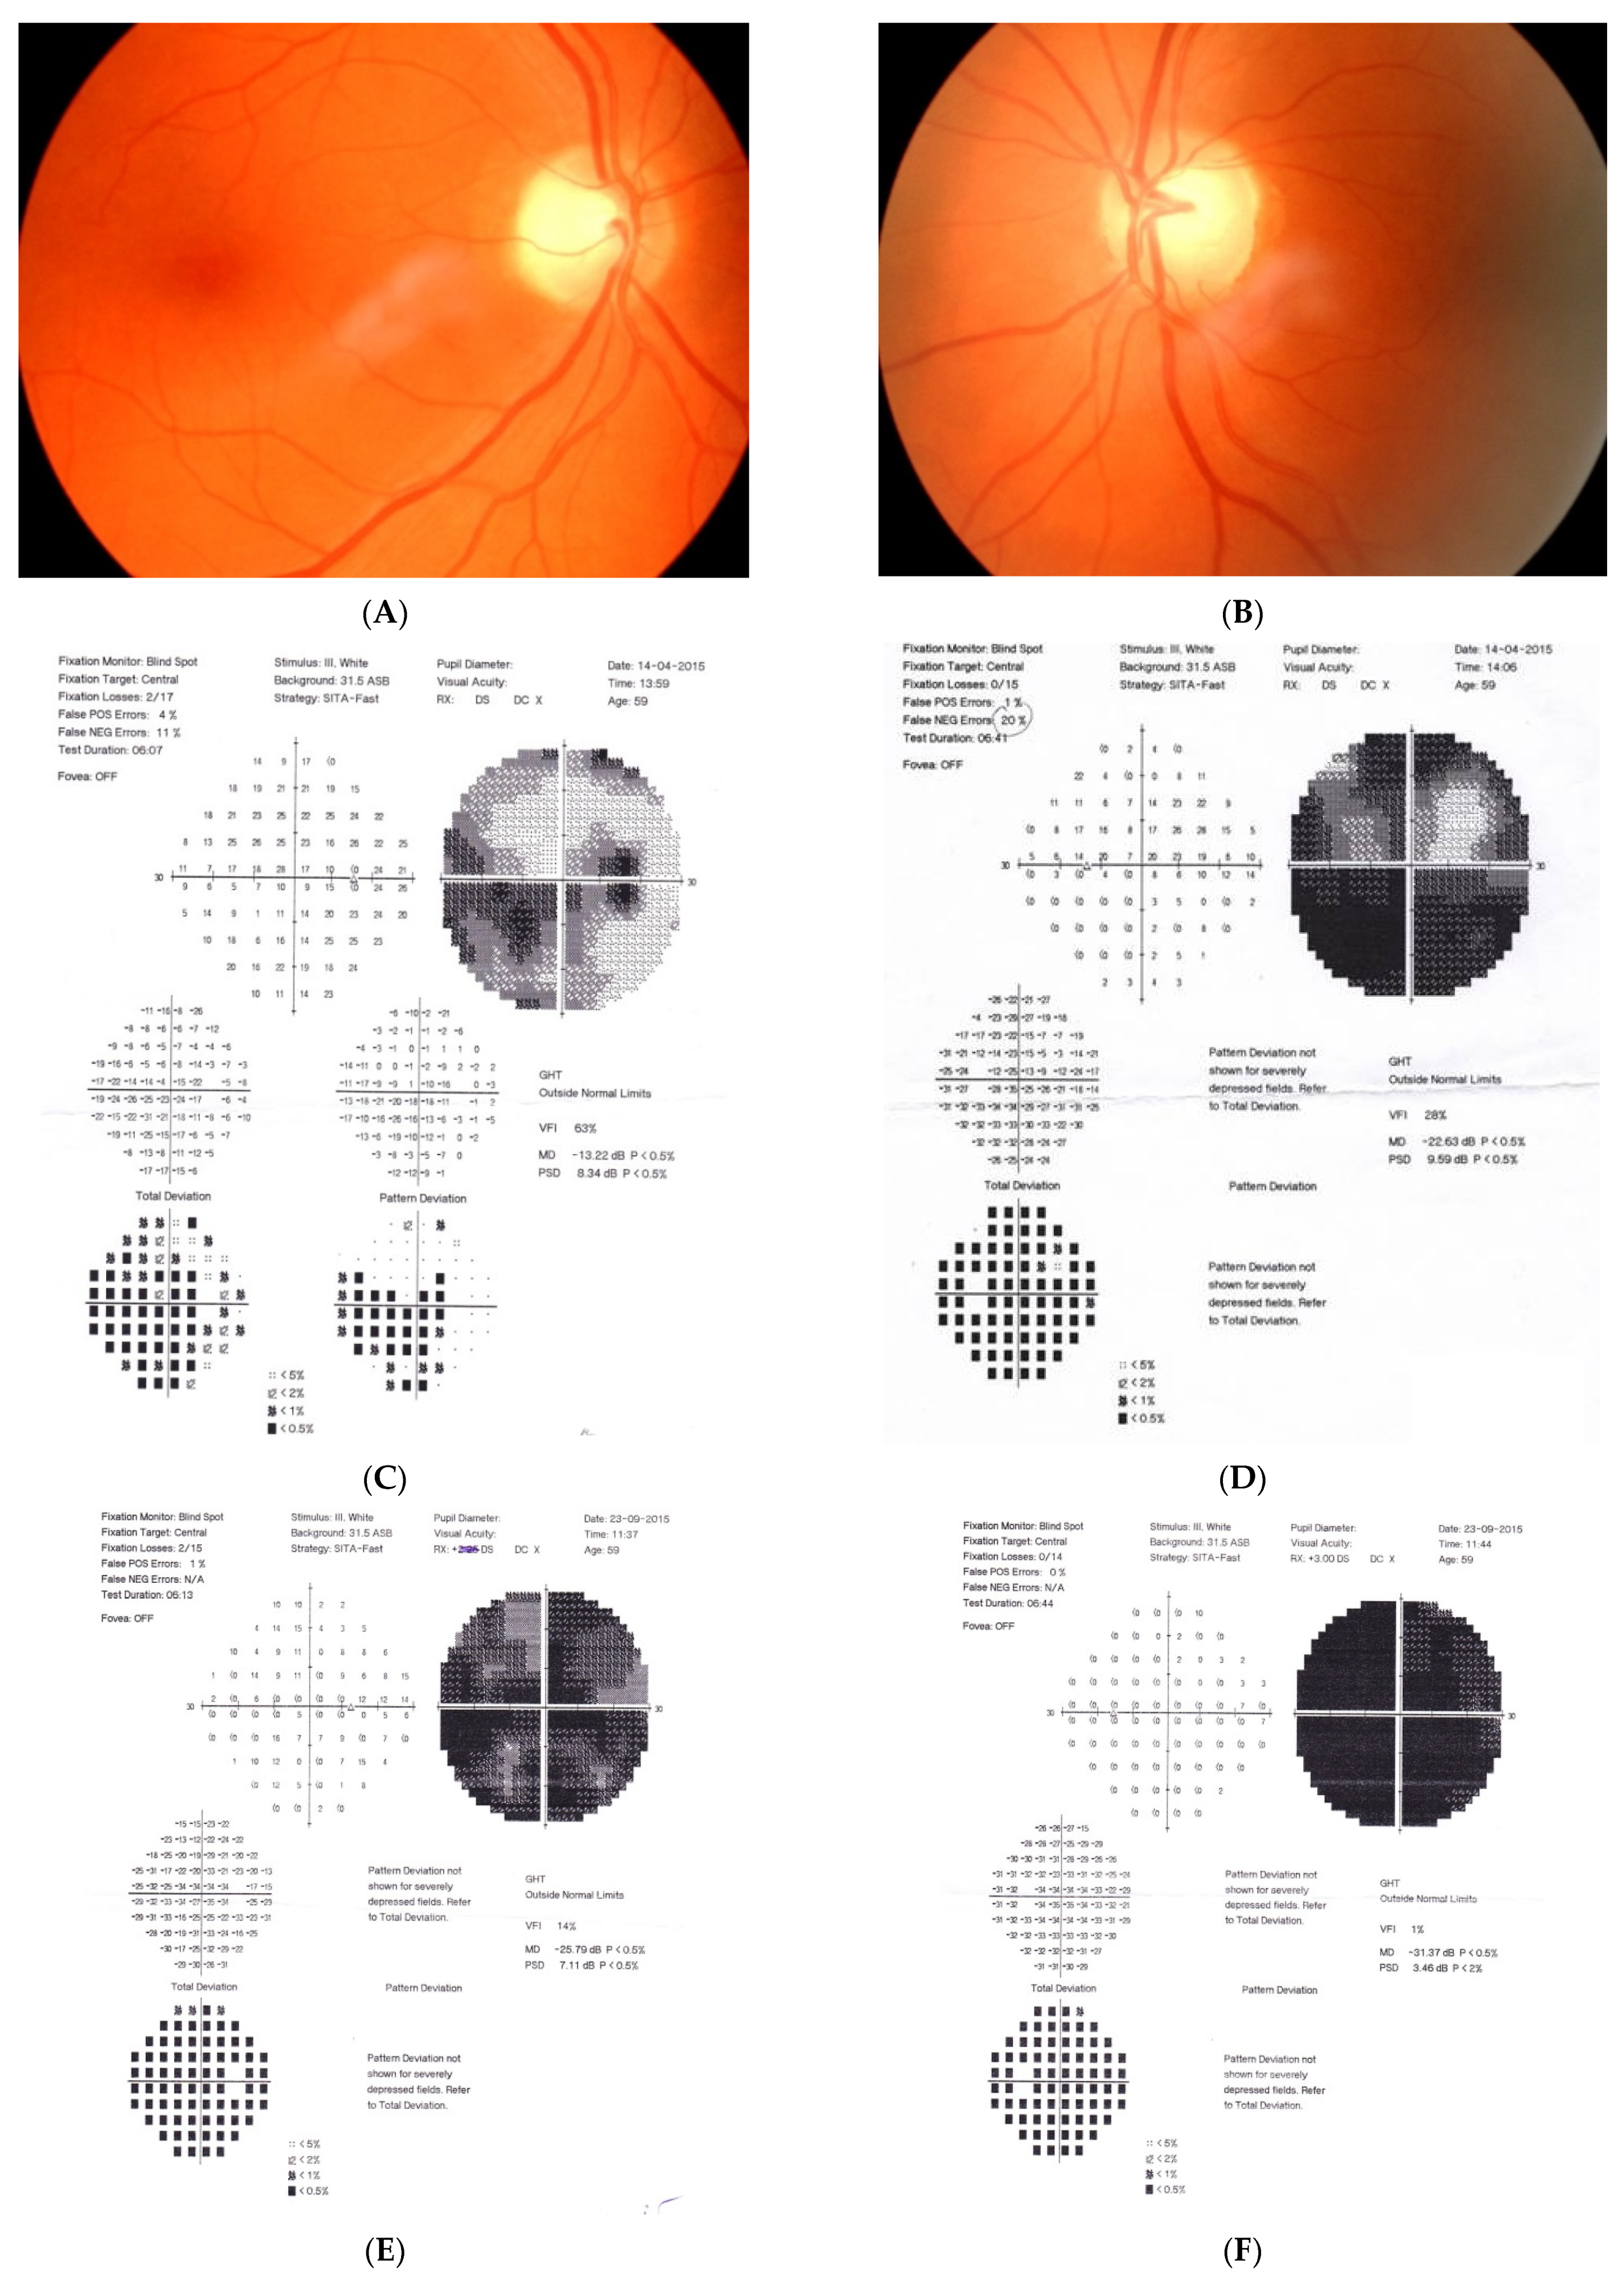

2.1. Case 1

2.2. Case 2